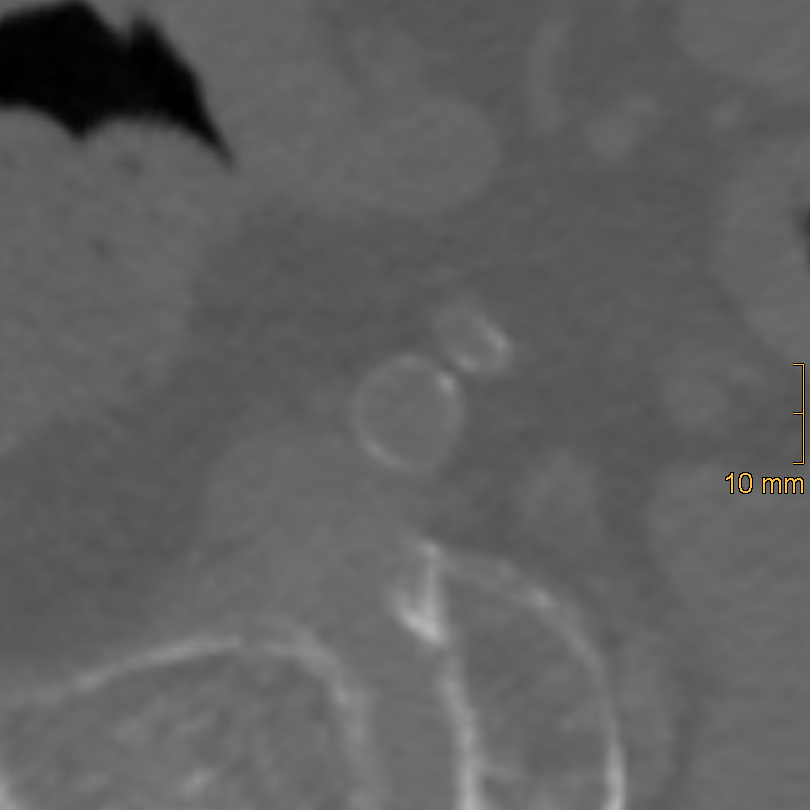

2.2.2. Iliac Artery Calcification